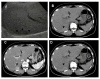

Case presentation: A 48-year-old Chinese female with underlying hepatitis B virus (HBV) infection was found to have a low echoic hepatic nodule by abdominal ultrasound. Tumor markers were negative. Dynamic liver computed tomography scans showed enhancement of the nodule in the arterial phase and early washout in the portal phase. Hepatocellular carcinoma (HCC) was considered based on the image findings and underlying HBV infection. However, the tumor biopsy revealed a malignant neoplasm that originating from neuroendocrine cells. Pre-operative and intra-operative investigations for the possible other origin of carcinoid tumor were negative, so PHCT was confirmed.